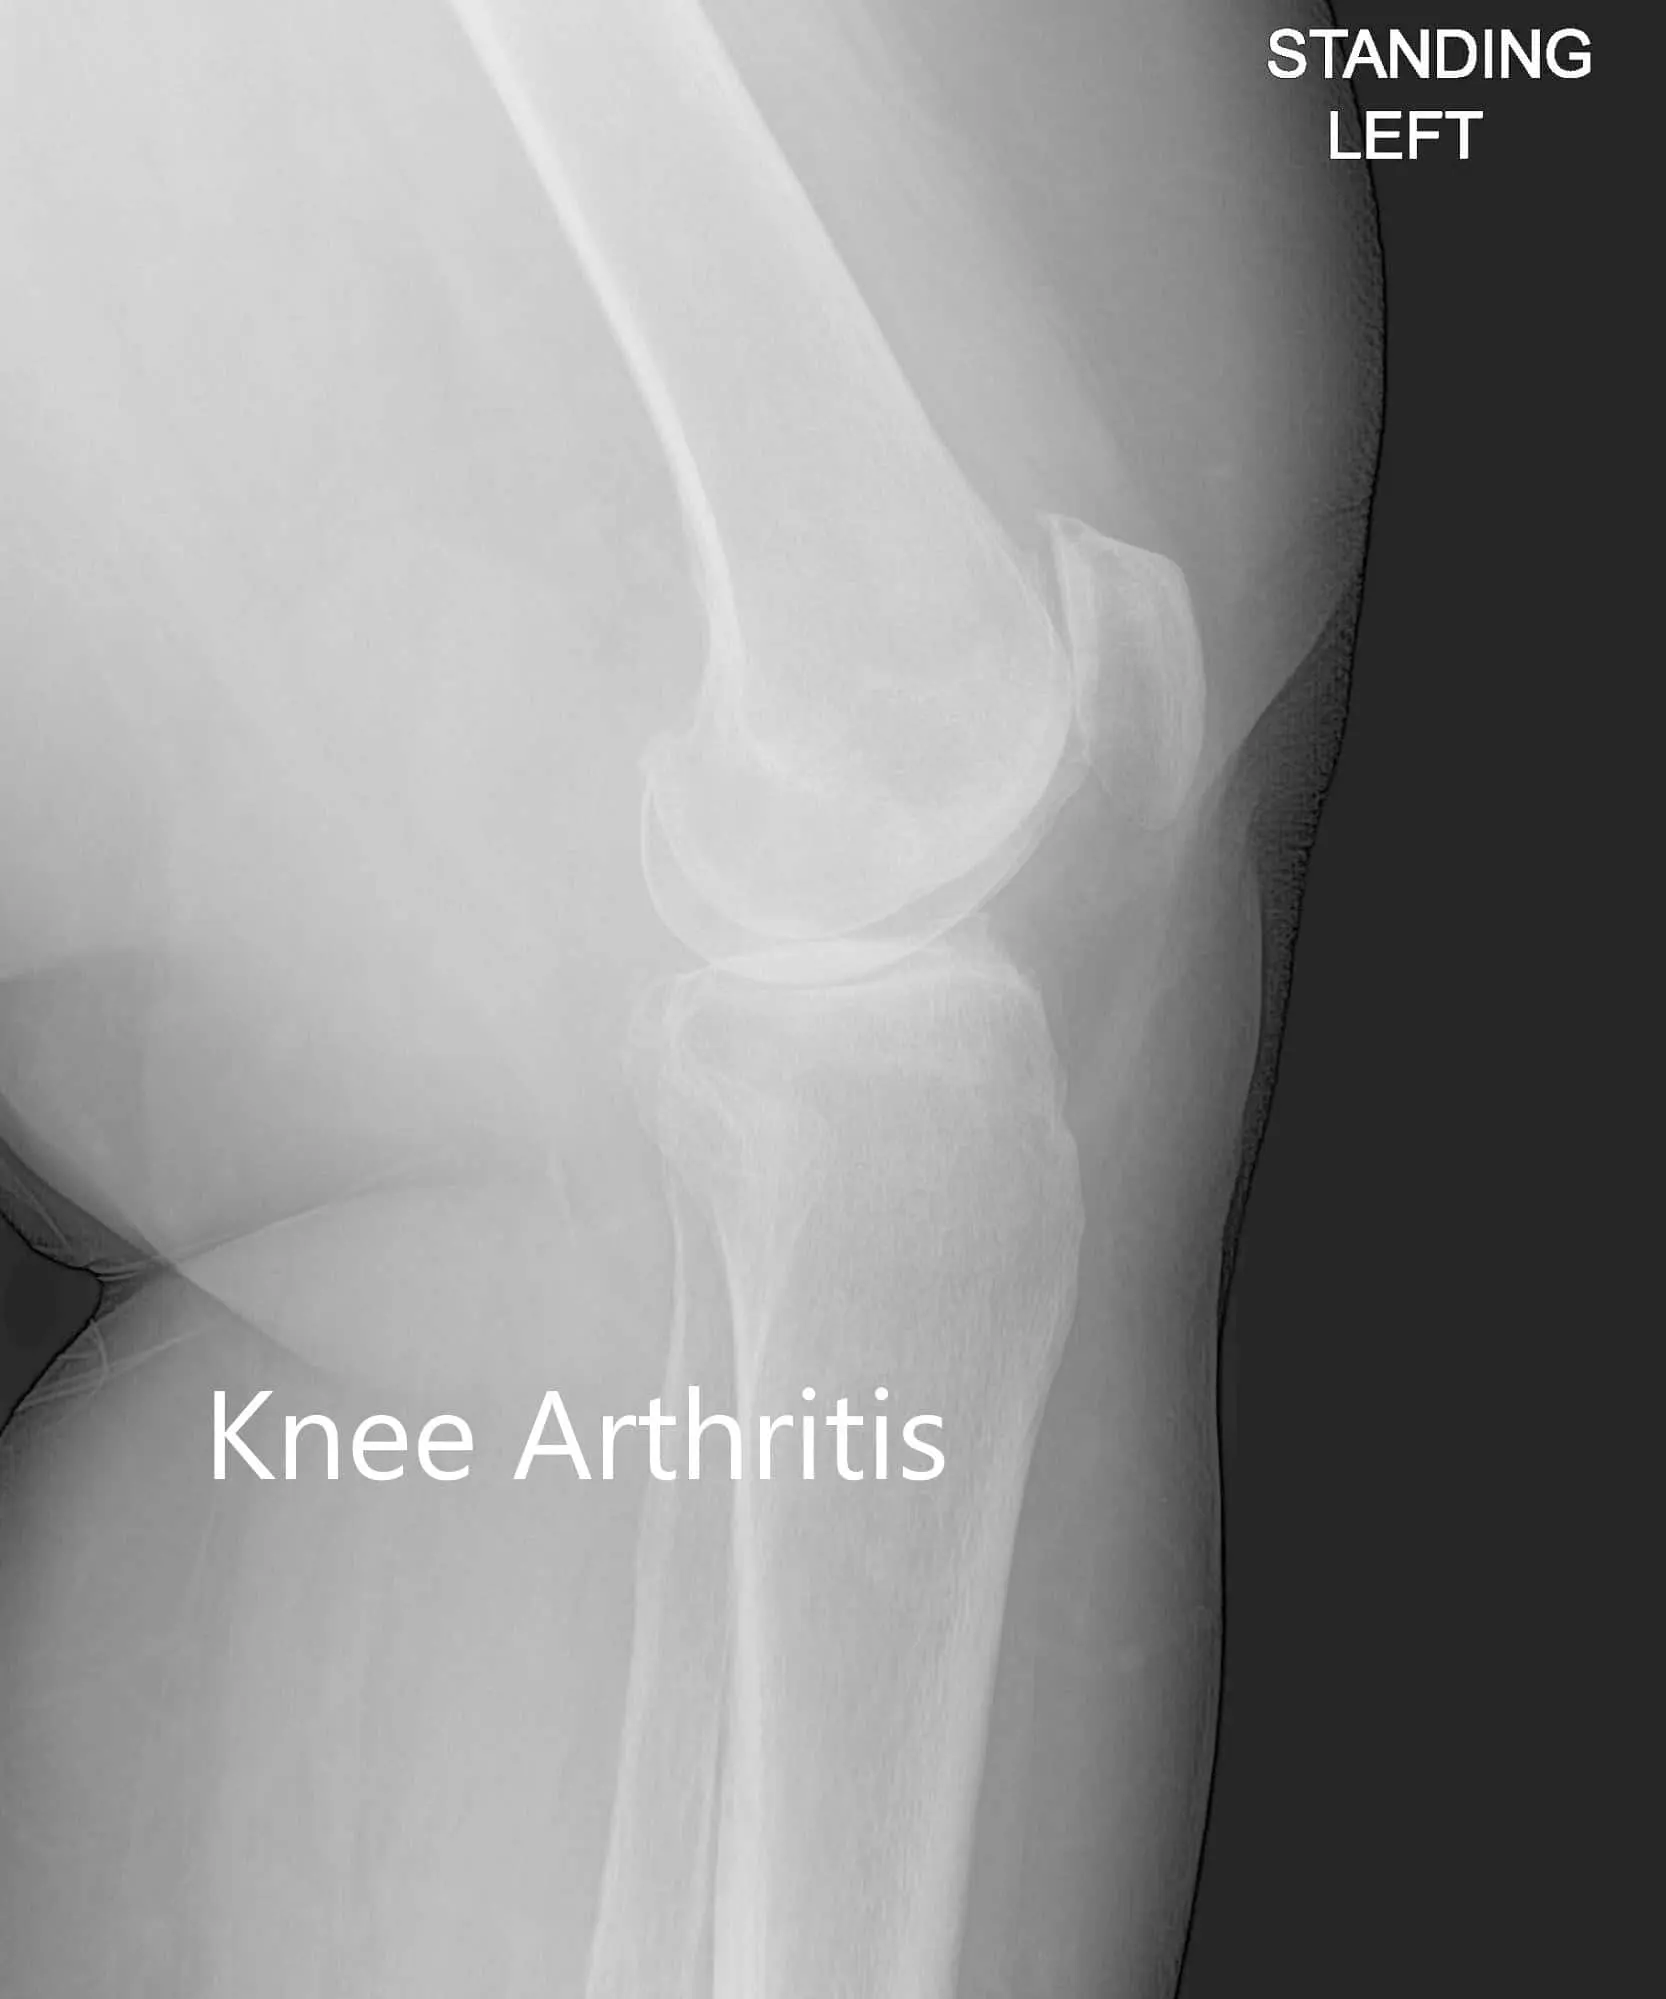

Imaging revealed severe tricompartmental osteoarthritis of the left knee with joint space reduction and osteophytes.

Anteroposterior and lateral view of the left knee